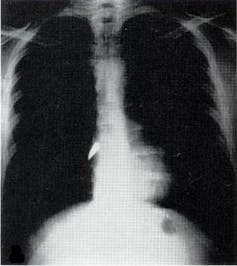

X-rays, a type of electromagnetic radiation, had been discovered in 1895 by Curie’s fellow Nobel laureate, Wilhelm Roentgen. As I describe in my book “Strange Glow: The Story of Radiation,” almost immediately after their discovery, physicians began using X-rays to image patients’ bones and find foreign objects – like bullets.

But at the start of the war, X-ray machines were still found only in city hospitals, far from the battlefields where wounded troops were being treated. Curie’s solution was to invent the first “radiological car” – a vehicle containing an X-ray machine and photographic darkroom equipment – which could be driven right up to the battlefield where army surgeons could use X-rays to guide their surgeries.